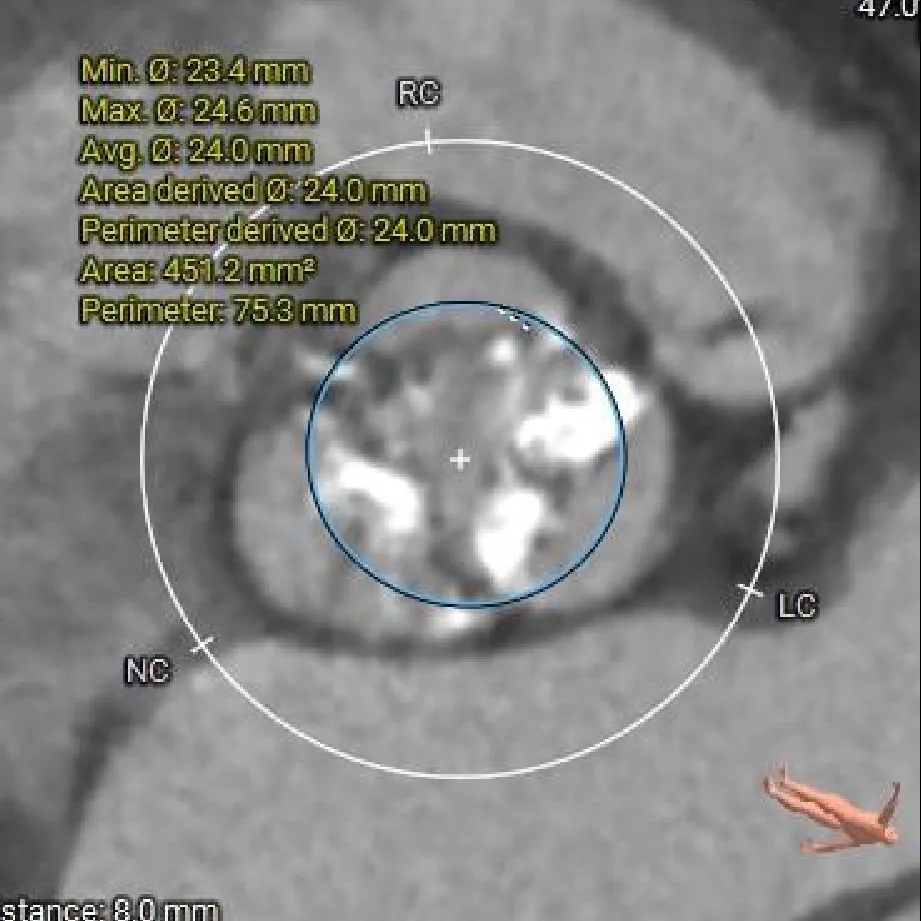

瓣上 8mm

24.0mm